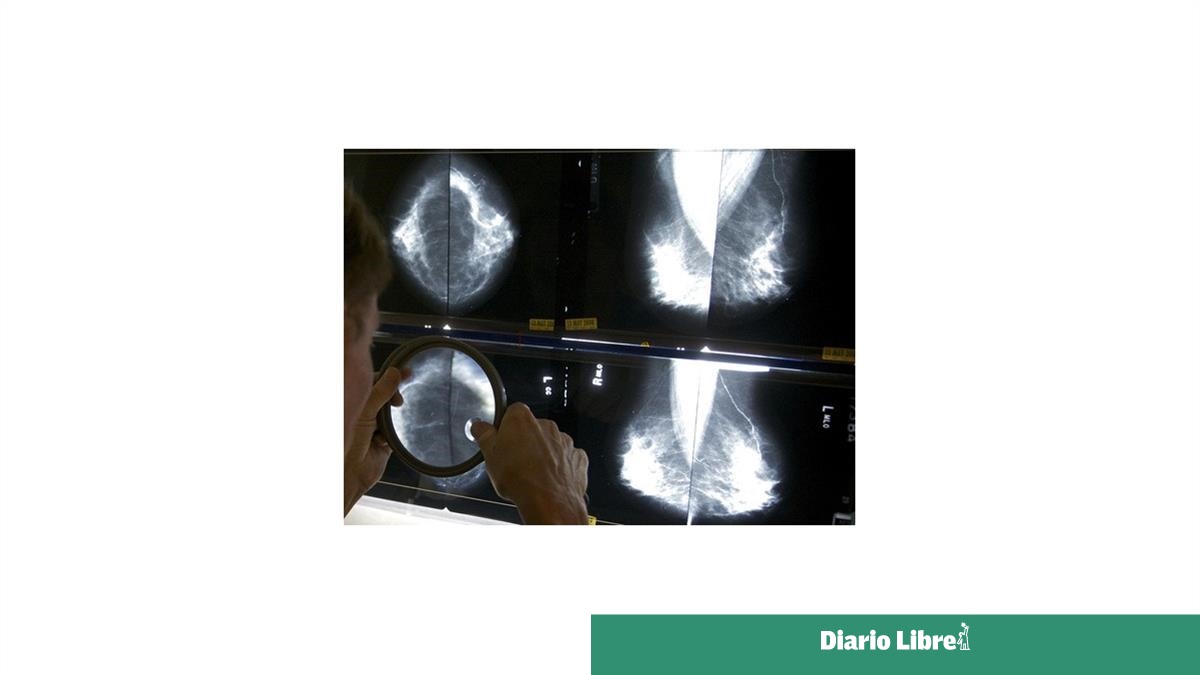

Todas las estadounidenses que se realicen mastografías recibirán pronto información sobre su densidad mamaria, que a veces puede dificultar la detección del cáncer.

Aproximadamente la mitad de las mujeres mayores de 40 años tienen mamas densas, con menos tejido adiposo y más tejido conjuntivo y glandular. Ese tejido aparece blanco en las radiografías, del mismo color que los tumores mamarios, lo que dificulta la lectura de las mastografías. El tejido mamario denso es uno de los factores que puede aumentar las probabilidades de que una mujer desarrolle cáncer.

Según las nuevas normas, las mujeres con mamas densas recibirán una nota escrita alertándolas de que su estado “dificulta la detección del cáncer de mama”. También se les indicará a esas pacientes que discutan los resultados con su médico.